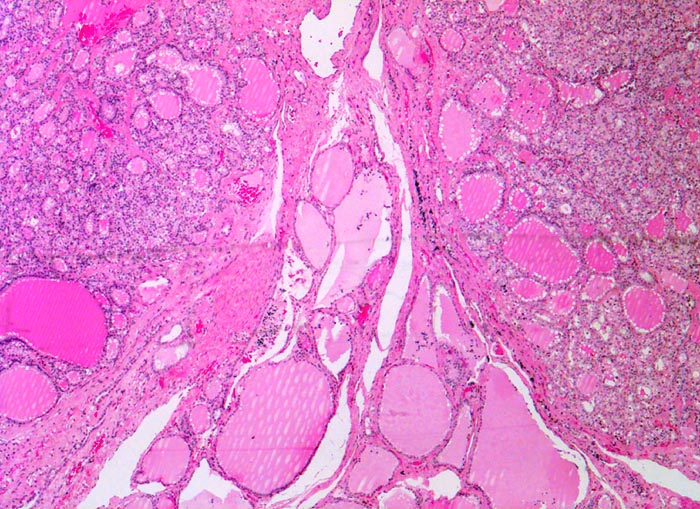

• Anschnitt eines grossen mikrofollikulären Knotens (autonomes Adenom) mit angedeuteter Kapsel und zentraler Einblutung. Oben zwei weitere kleine Satellitenknoten.

• Kompression des angrenzenden Schilddrüsenparenchyms. Dieses besteht aus grossen Follikeln mit kubischem oder abgeflachtem Epithel und reichlich kompaktem dunklem Kolloid in den Follikellumina.

• Zeichen gesteigerter hormoneller Aktivität im Adenom:

• Kleine Drüsenlumina.

• Teils mehrreihiges kubisches bis zylindrisches Epithel.

• Fehlendes oder nur spärliches helles Kolloid mit zahlreichen Resorptionsvakuolen.